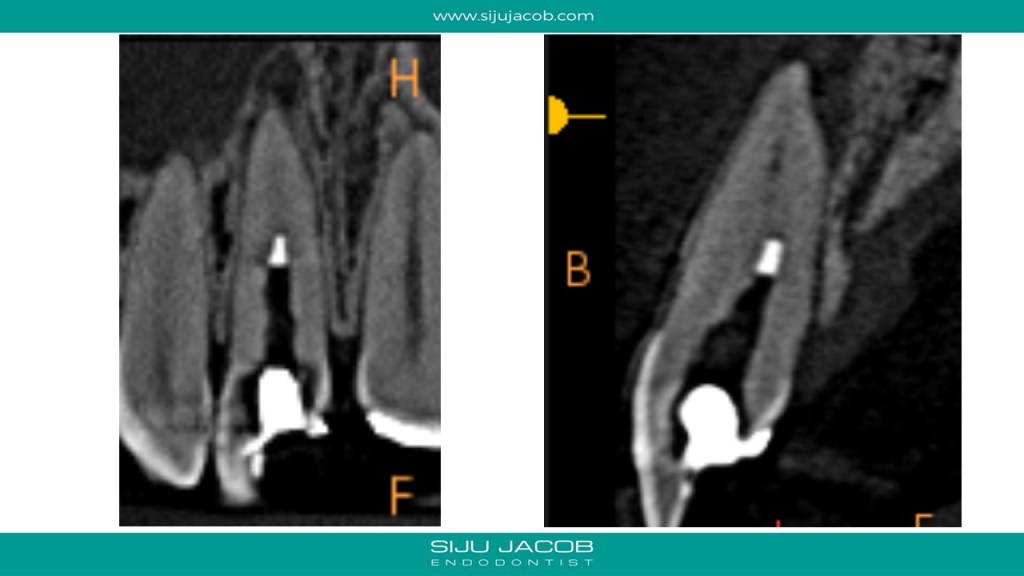

This case was calcified all the way to the apical one third. As we go deeper, the labio-palatal orientation becomes a problem and as we approach the apical part, the margin for error decreases. In this case, I took an inter-appointment CBCT to see the location of the canal. The video explains the whole process.

And here are the pics for the case: